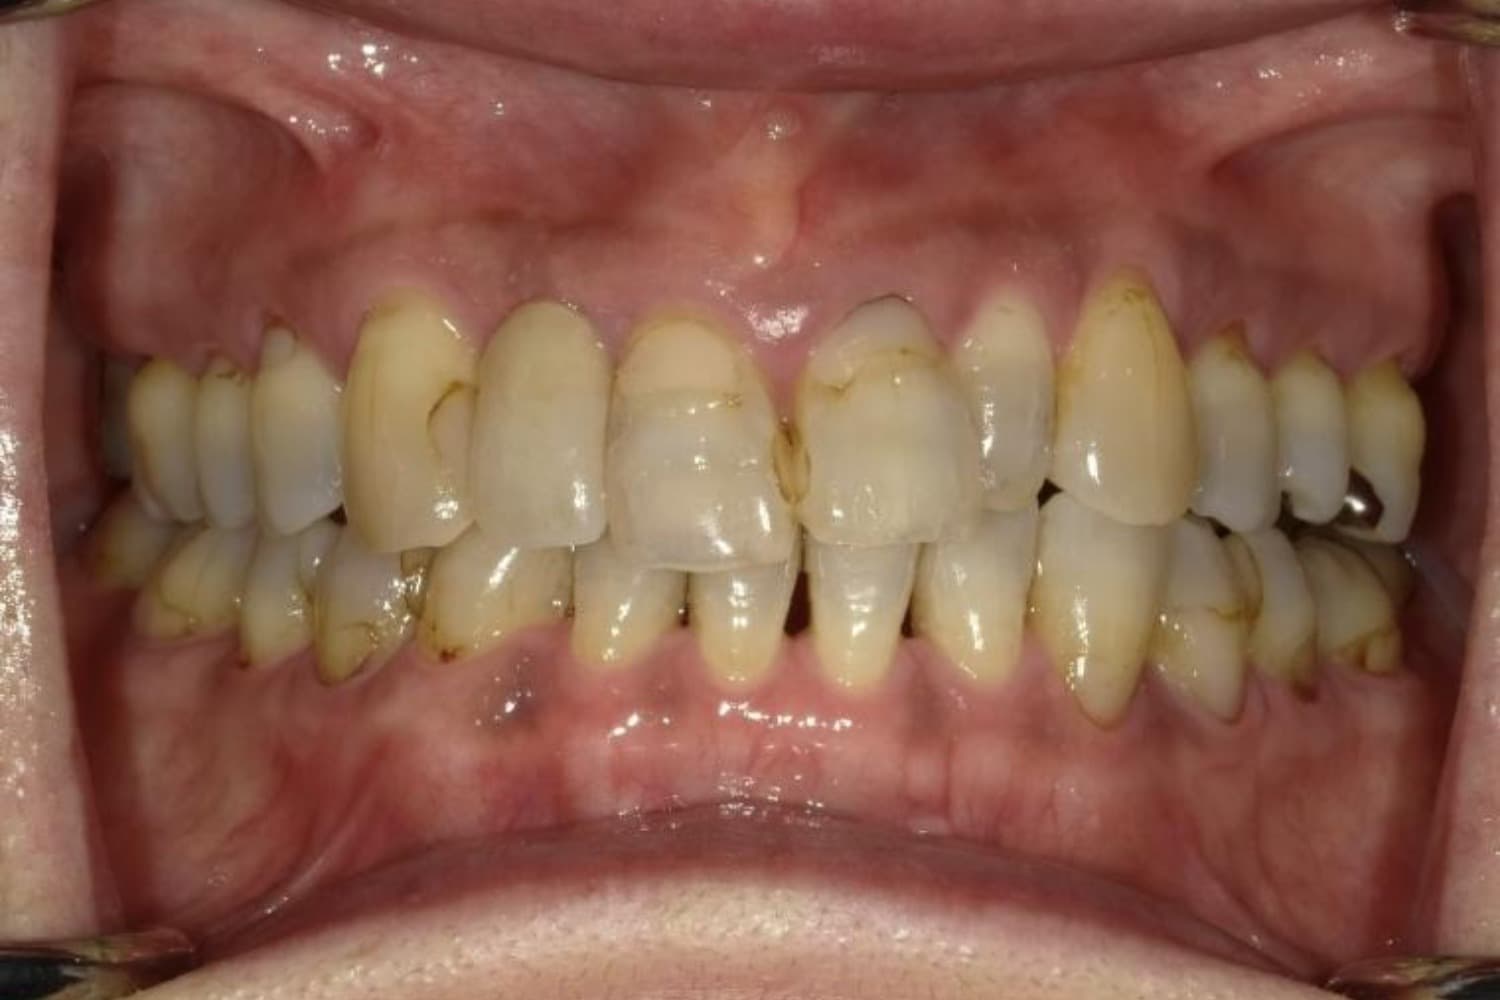

ガタガタとした歯並びや八重歯(1)

Before

After

ガタガタとした歯並びや八重歯をマウスピース矯正(インビザライン)にて治療

主訴

下の前歯のガタガタが気になる

治療期間

2年5カ月

費用

90万円

副作用・リスク

・矯正治療による歯の動きには個人差があり、想定より治療期間が延びることがあります。 ・矯正治療で歯を動かす際に痛みをともなうことがあります。 ・指示された通りに保定装置を装着しないと、歯並びや噛み合わせの後戻りを引き起こす可能性があります。